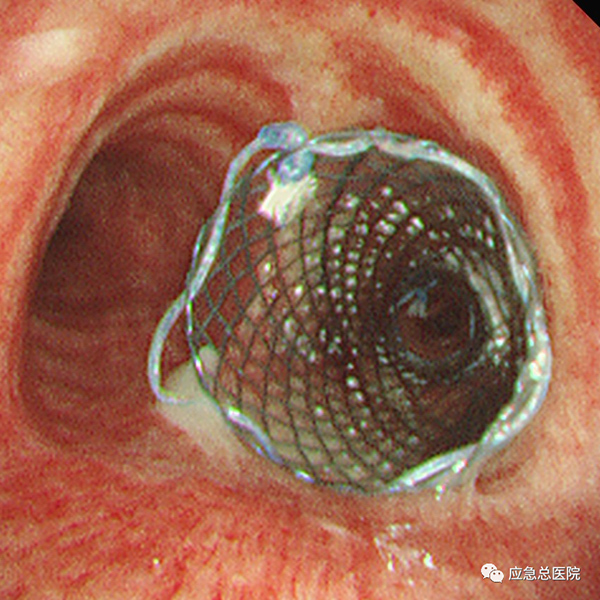

气管镜下支架置入手术可以用于食道癌、肺癌、甲状腺癌等各种肿瘤引起的气道狭窄;其他疾病所致的气管、支气管瘘等良性气道狭窄。可以有效缓解患者气急、胸闷等呼吸困难症状,从而提高患者的生活质量,并为后续治疗提供宝贵机会。与外科手术相比,气管镜下支架置入技术具有不开刀、创伤小、操作简便、安全性高、术后恢复快、并发症少等显著优点。对于无法手术及无法耐受手术的恶性肿瘤患者,该方法创伤小,出血少,病人耐受性较好,可缓解症状,达到姑息治疗的目的。

(1)经气道介入技术:硬质支气管镜、氩气刀、二氧化碳冷冻、球囊扩张、激光、低温等离子射频、微波、气道支架置入及取出、放射性粒子植入、局部药物注射、光动力治疗、各类气道瘘口的封堵等,全面解决患者的气道梗阻及气道瘘问题。同时对慢阻肺(COPD)终末期患者予以支气管镜下单向活瓣肺减容术、热蒸汽消融肺气肿减容术,并对难治性哮喘患者行支气管热成形术,提高患者生活质量。